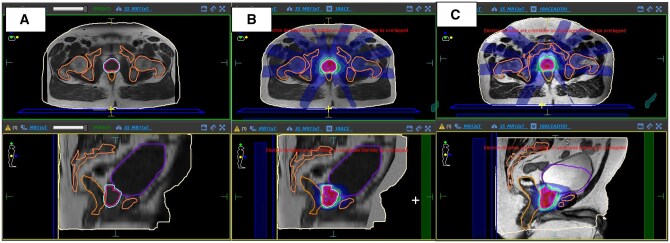

Methods: We audited prostate cancer patients treated with 5-fraction (#) stereotactic body radiotherapy (SBRT) between March 2023 and January 2024, assessing dMRI for RT planning suitability. Planning suitability required a T2-weighted sequence for target/organs at risk (OAR) delineation and a large field-of-view (LFOV). Scans were classified as RT plan suitable or as having specific issues (incomplete body coverage or slice thickness >10 mm). Workflow analysis from RT referral to first fraction estimated potential time savings with simulation-free RT (SFRT). Case studies illustrated identified issues and proposed solutions.

Results: dMRIs were available for 93% of patients, with scans originating from various hospitals and conducted on 1.5 Tesla (T) or 3 T MRI scanners. Ideal image characteristics for RT planning were met in 38% of MRIs. Issues such as cropped field of view (FOV) and low slice resolution were identified, but proposed solutions could increase the number of patients with suitable scans to 87%.